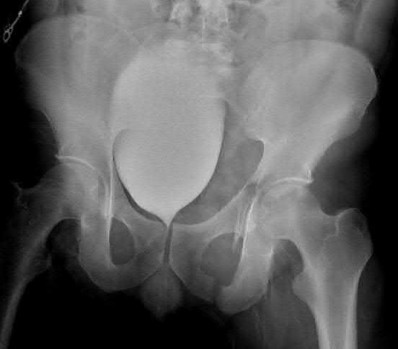

Question 11

A poly-trauma patient presents hemodynamically unstable with an anteroposterior compression (APC-III) pelvic ring injury. A circumferential pelvic binder is requested to reduce pelvic volume and control hemorrhage. To be anatomically effective, the binder must be centered precisely over which of the following landmarks?

Explanation

For optimal mechanical advantage and effective reduction of an 'open book' pelvic fracture (APC type), a pelvic binder must be applied directly over the greater trochanters of the femurs. Applying it higher, such as over the iliac crests, is a common error that fails to adequately close the pelvic ring and can paradoxically open the true pelvis.